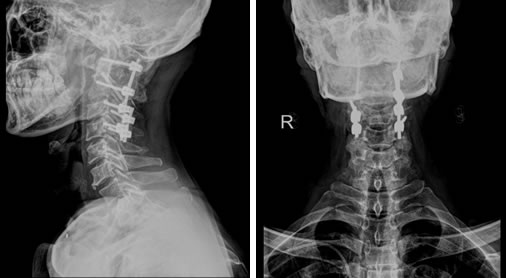

上颈椎的解剖结构非常复杂,周围有众多的主要神经、血管,手术操作时稍有不慎,就可能招致灾难性的后果,加上患者寰椎后弓的发育不全,造成延髓处骨性屏障缺失,以及显露、置钉时的解剖标志丧失,极大地增加了手术的难度以及风险。为保障安全,医院根据患者高精度CT三维扫描的原始数据,依托院外高新科技3D打印实验室,制作出1:1的上颈椎模型,真实还原了患者上颈椎骨折及畸形的情况。根据3D打印模型,骨科团队在陈飞博士的主持下进行多次的模拟手术,在毫米级别上,精确地定位了内固定物的置入点、明确了螺钉的方向、直径和长度,并对手术中可能出现的意外作了充分的估计和预演。

5月8日,决定治疗成败的关键一天到来了。因手术是经后路进行,需要神经外科的特殊头架固定,治疗团队特邀本部神经外科江常震副主任医师指导头架的使用及固定。手术由骨科陈飞博士主刀,历时约5小时,出血仅150ml,麻醉清醒后,病人四肢感觉、运动功能正常,生命体征平稳,表明未损伤颈髓和椎动脉。术后,患者颈部疼痛明显缓解,术后一天就拔除了气管插管,回到普通病房,并可以自行坐起。